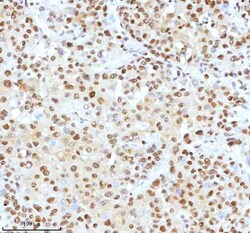

Reconstitute with 0.2 mL of distilled water to yield a concentration of 500 μg/mL. Positive Control - WB: human LNCAP whole cell, human Hela whole cell, human 293T whole cell, human HepG2 whole cell, human Jurkat whole cell, human K562 whole cell, human A549 whole cell, human A431 whole cell. IHC: human bladder cancer tissue, human bladder cancer tissue, human colon adenocarcinoma tissue, human colon adenocarcinoma tissue, human glioblastoma tissue, human glioblastoma tissue, human liver cancer tissue, human liver cancer tissue, human lung adenocarcinoma tissue, human lung adenocarcinoma tissue, human pancreas ductal adenocarcinoma tissue, human pancreas ductal adenocarcinoma tissue, human testicular seminoma tissue, human testicular seminoma tissue. ICC/IF: U2OS cell. Flow: A431 cell. Store at -20°C for one year from date of receipt. After reconstitution, at 4°C for one month. It can also be aliquotted and stored frozen at -20°C for six months. Avoid repeated freeze-thaw cycles.